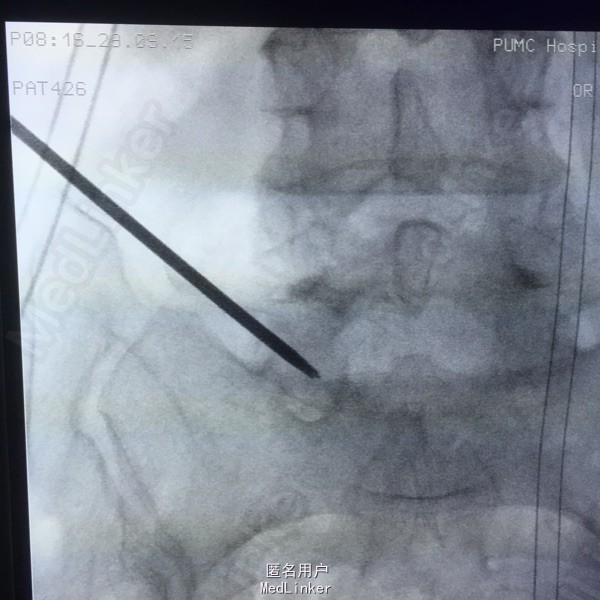

65岁女性,右下肢放射性疼痛2年半,保守治疗效果不佳 2年前曾行C5-6的ACDF术。

L5-S1左侧棘旁压痛(+),右小腿外侧针刺觉稍弱,右侧跟腱反射稍弱。 腰椎CT提示L5-S1间盘突出,偏右侧。 腰椎X线片提示髂嵴偏高,L5横突肥大。

L5-S1椎间盘突出 C5-6 ACDF术后 拟行椎间孔镜手术

因为穿刺通道比较狭小,进入椎间盘时偏杨氏,采用由内而外的方式减压神经根,用镜下弹性弯钳较好完成了神经根减压。